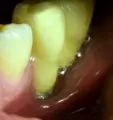

Подскажите, пожалуйста, можно ли по панорамному снимку определить правильность установки импланта? Имплант устанавливался на место шестерки, верхней челюсти, закрытый синус-лифтинг, с 1 гр. кости. Сколько по норме миллиметров должно быть между корнем зуба и имплантом? Является ли нормой, что после снятия швов, языком нащупывалась точка импланта, а вскрытие было бескровное?

В вашем случае поврежден корень зуба и необходимо срочно извлечь имплантат. Ответы на другие вопросы не актуальны. Это, что касается нижнего имплантата. На верхней челюсти я не вижу качественной операции, закрытый синус, так как имеется перфорация на 2 мм. пазухи. Рекомендую обратиться к хирургу.